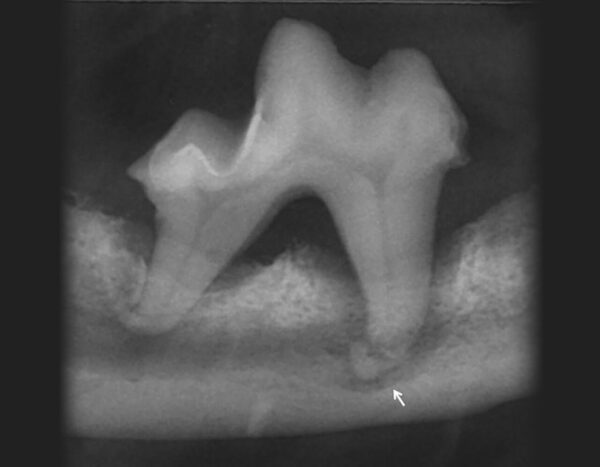

La radiología es indispensable en esta enfermedad, ya que es la única manera de detectarla en la superficie de la raíz. Es una lesión muy común en gatos y que se caracteriza por la destrucción progresiva del tejido dentario por activación de los odontoclastos. Según Verstraete (1998) hay un 8,7 % de gatos con LR que no se diagnostican al no hacer radiografía.

El Colegio Dental Veterinario Americano (AVDC) las clasifica en cinco estadios según la gravedad y localización de la lesión, y en tres tipos según su apariencia radiológica:

- En relación con la apariencia radiológica, en el tipo 1 veremos radiolucidez focal o multifocal en el diente. El resto del diente no está afectado y el espacio del ligamento periodontal no presenta alteraciones.

- En el tipo 2 veremos un estrechamiento o desaparición del espacio del ligamento periodontal en algunas áreas y disminución de la radiopacidad de parte del diente.

- En el tipo 3 observaremos las apariencias y características de los tipos 1 y 2 en un mismo diente (imagen 13).

La apariencia radiológica es importante, ya que es decisiva para el tipo de tratamiento que debemos llevar a cabo: la extracción en el caso de tipo 1 y la amputación coronal en el tipo 2.